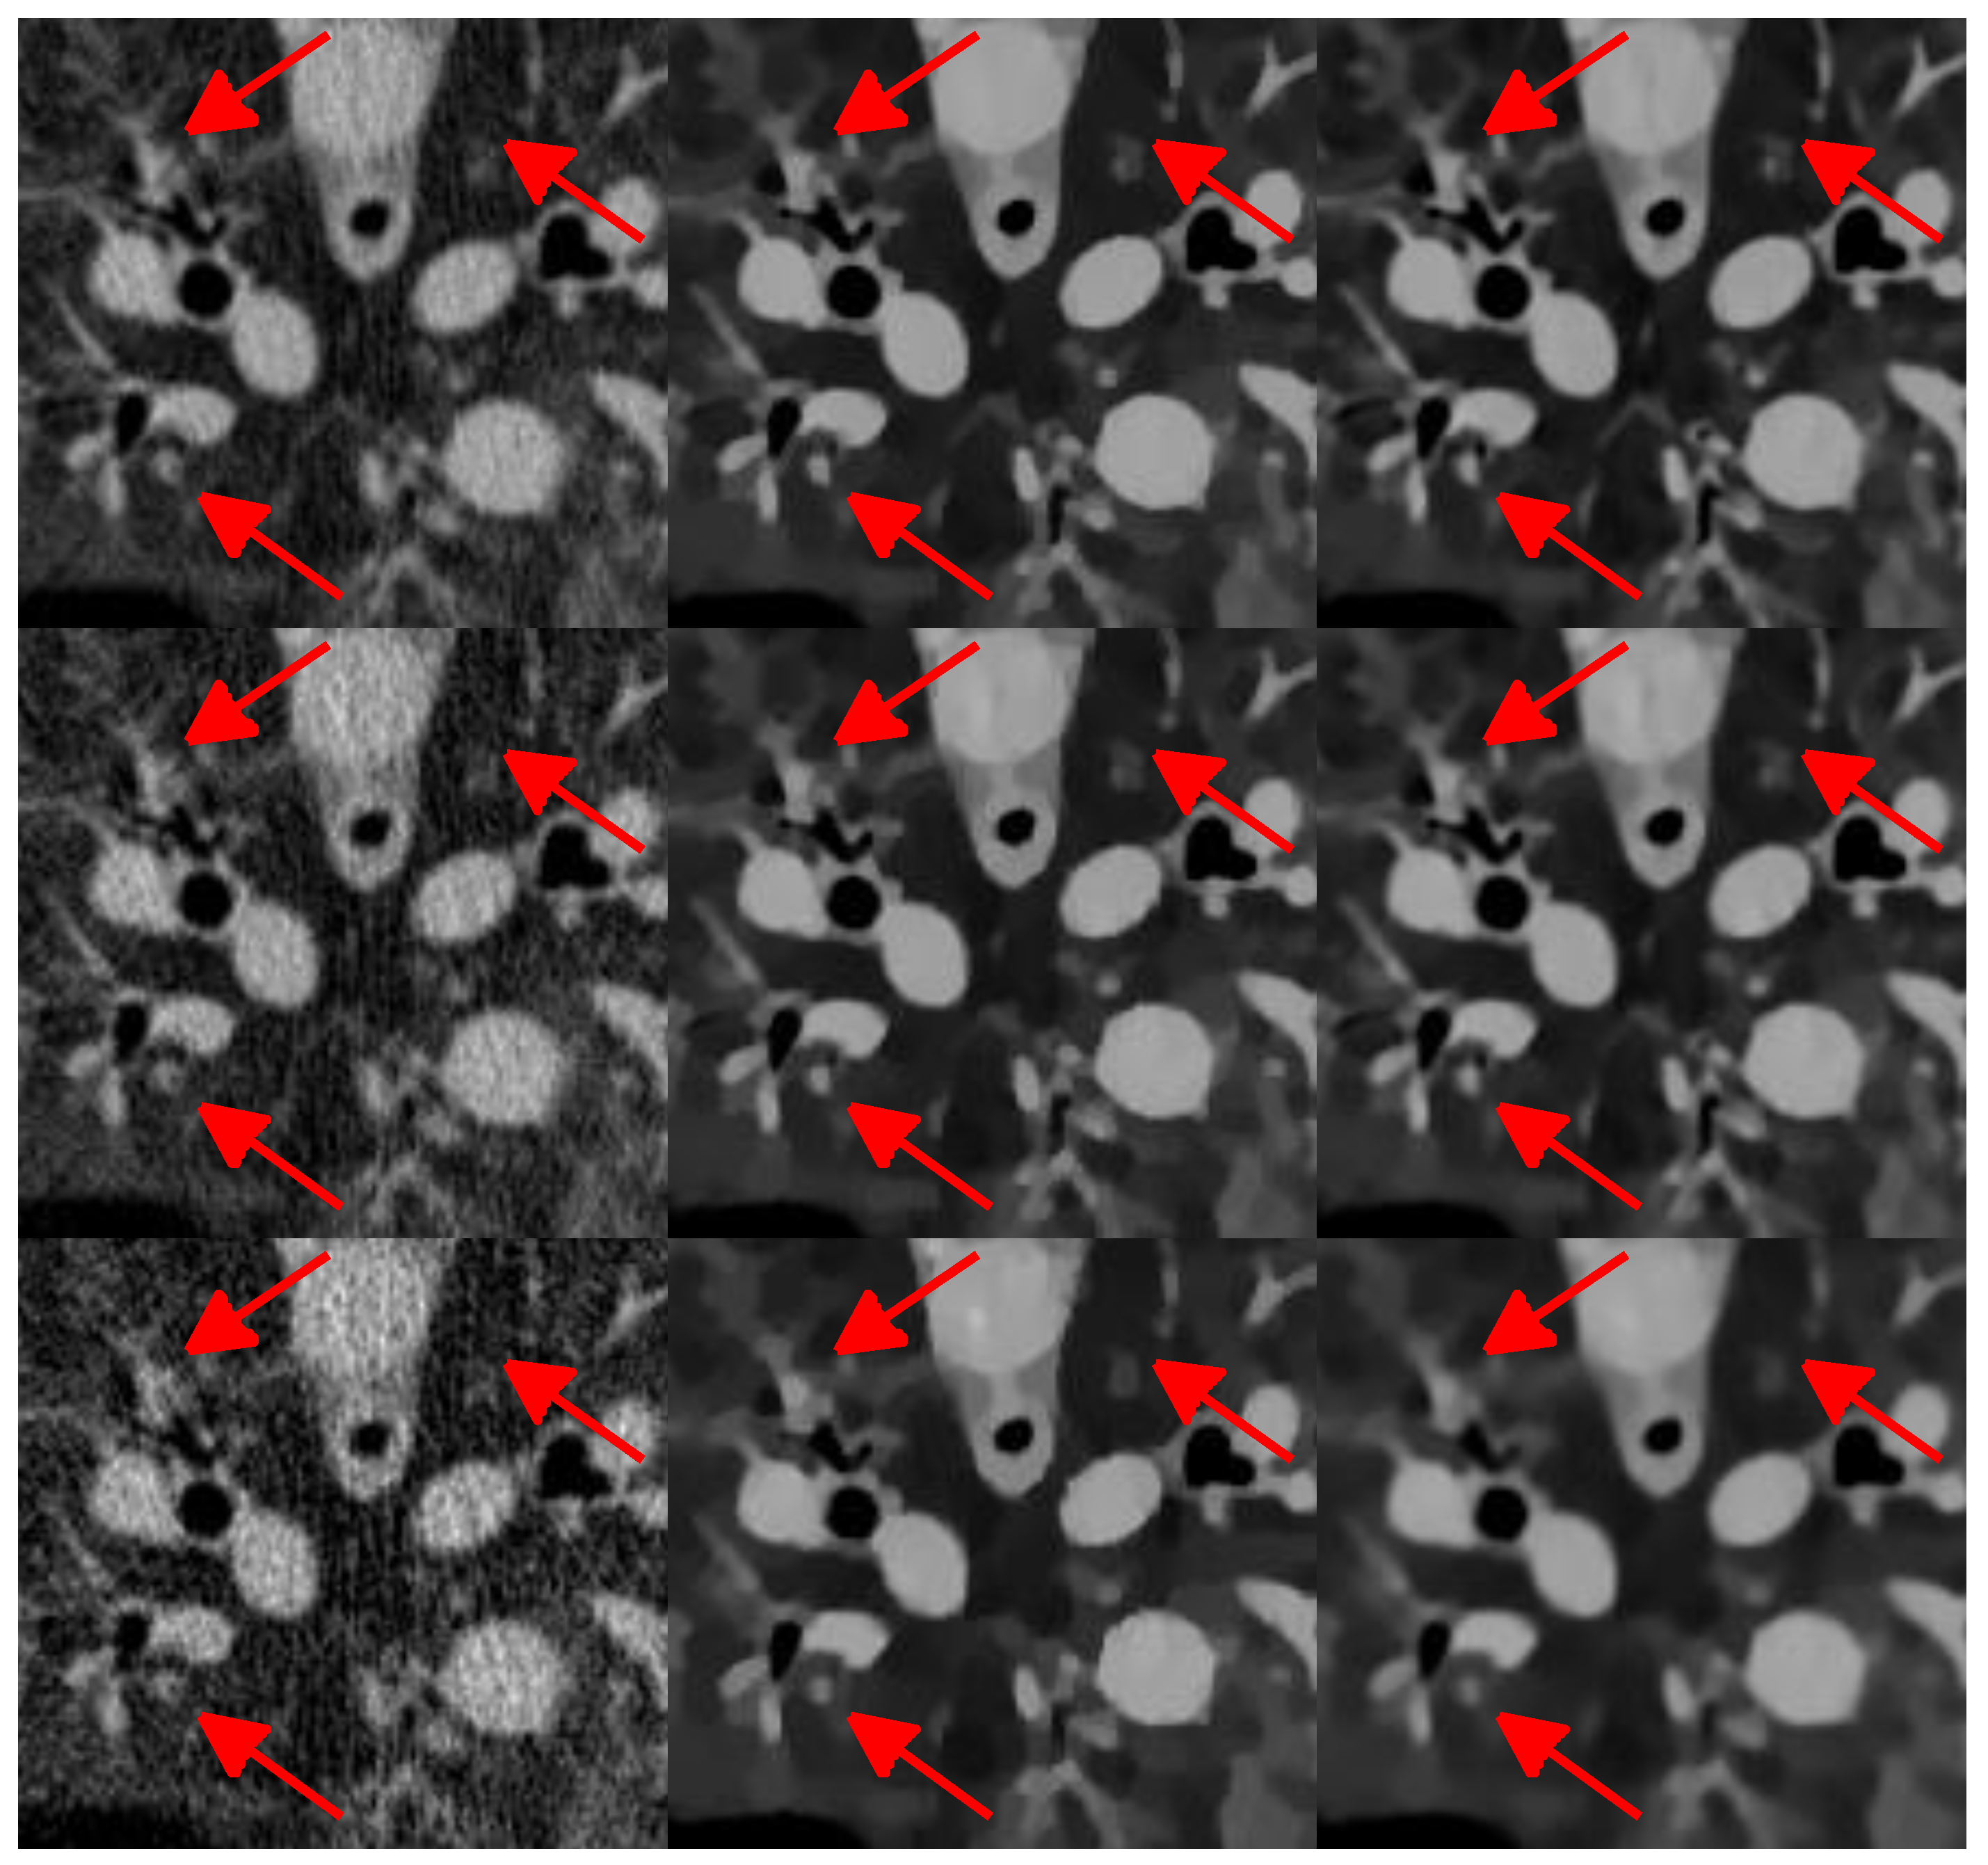

The reconstruction results are presented in Figure 10. It can be seen that the FBP results look very noisy and became worse and worse when the number of projection views decreased from 1160 to 290. Both the SIR-TV and our SIR-STV1 method outperform the FBP algorithm in suppressing image noise. To clearly compare the reconstruction performance of all algorithms, ROIs are extracted from Figure 10 and magnified in Figure 11. From Figure 11, especially denoted by red arrow regions, we can observe that the SIR-TV method produces patchy artifacts obviously, while the SIR-STV1 method could avoid the patchy artifacts effectively.

Figure 11. Zoom in view ofregion of interest(ROI) in Figure 10.